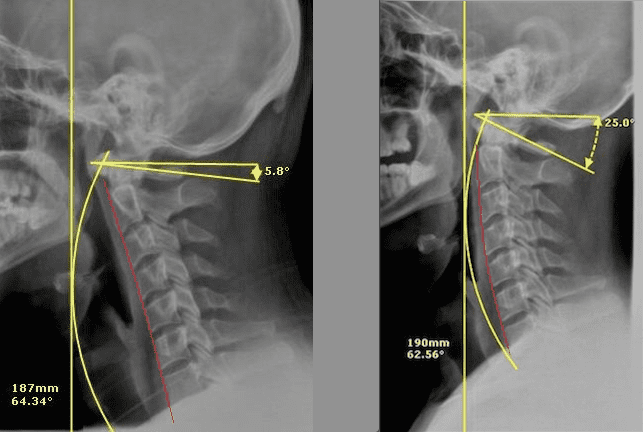

- Motion X-ray and pictures if we find nerve irritation

- Low-radiation video X-rays